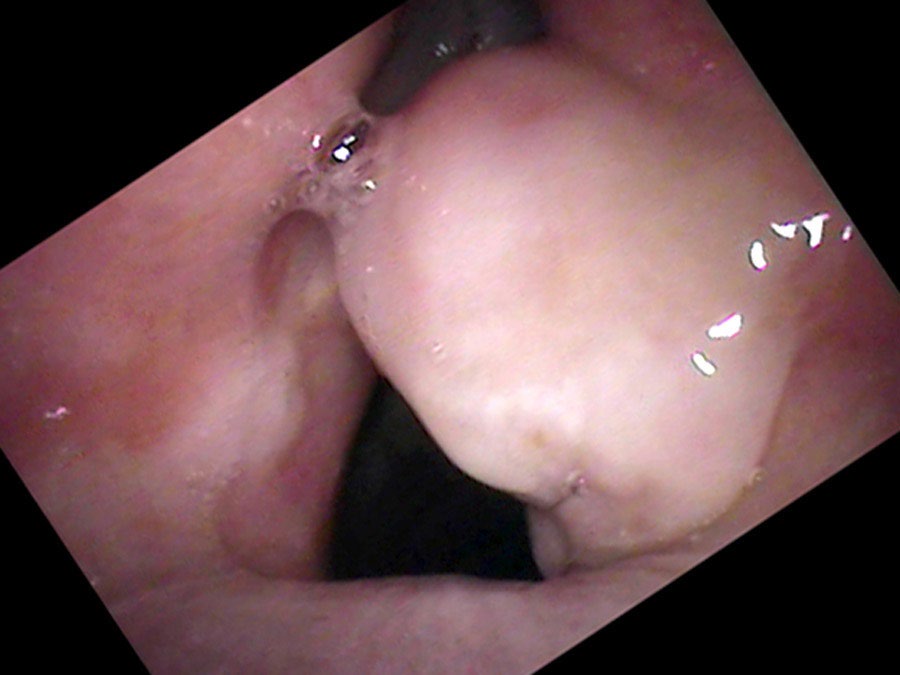

On endoscopy, there is a surprisingly large lump on the right vocal process — a yellow ball of tissue sitting just above an ulcerated groove in the cartilage.

It really isn’t a growth. It is a collection of blood vessels wound into a little ball — what surgeons call “proud flesh” when it forms on the outside of the body.

There is one particular type of vocal cord lesion that may start with a temporary pain and is located at the back of the larynx — most commonly on the cartilage called the vocal process of the arytenoid, right at the end of the vibrating portion of the vocal cord. It is not really a growth. Rather it is a collection of blood vessels wound into a little ball — called proud flesh when it forms on the outside of the body. When something traumatizes the mucosa, eroding through it and exposing the cartilage, an ulcer forms. Then granulation tissue heaps up around the traumatized point as a reaction to an open wound exposed to the bacteria of the mouth and throat.

From injury to resolution, granulomas follow a predictable evolution. New ulcers from overuse initially split into two parts where the opposite vocal process rests in a groove during closure. Gradually, granulation tissue heaps up around the traumatized point, forming a mass. In the middle of their lifespan granulomas become yellow or red and round. Later the mass tends to harden, become white and spherical, and the base narrows to a stalk. At this stage the granuloma may flip up out of the way during phonation and no longer impairs closure — so vocal capabilities testing can return to normal even while the granuloma is still present.